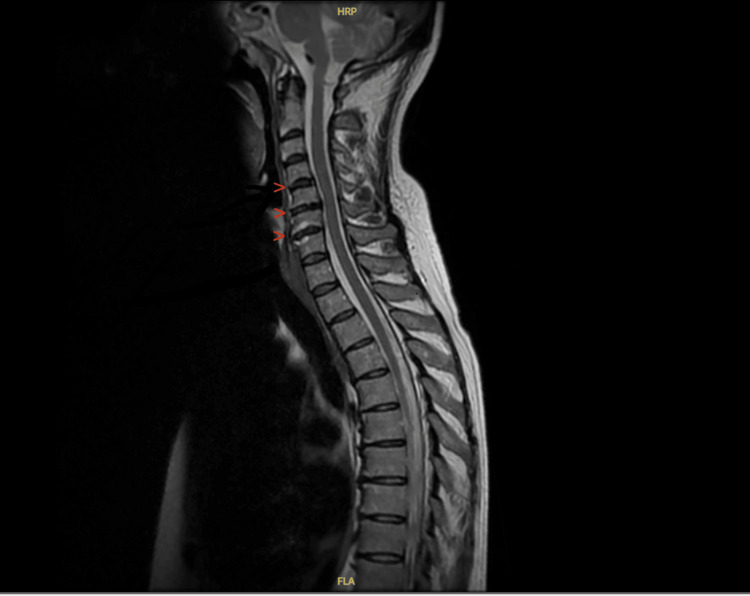

一个63岁的女性患者提出了急性医疗单位似乎是一个渐进的行动能力下降的情况下,一个常见的,往往非特异性的表现在急性医学。她描述了上肢和下肢无力和麻木影响了她的行走能力。最初,她的上肢麻木在社区治疗为尺神经压迫。她全年还多次出现呼吸短促,最初在社区中作为疑似哮喘加重加以处理;然而,她的症状是非特异性的。常规调查显示严重嗜酸性粒细胞增多(13.37 × 10⁹/L)、贫血和白细胞增多。神经生理学证实多发性单神经炎,进一步的自身免疫检测显示抗中性粒细胞胞浆抗体(P-ANCA)阳性和髓过氧化物酶(MPO)抗体升高。最终诊断为嗜酸性肉芽肿病合并多血管炎(EGPA),这是一种罕见的表现,挑战了最初的诊断假设。本病例是一个例子,说明并非所有EGPA的表现都是直截了当的,并且在急性医疗环境中可能会错过它。通过本病例报告,我们想强调 EGPA多发单神经炎的微妙和经常模糊的性质。我们还想强调延迟诊断对EGPA患者的影响,以及这如何影响患者的长期健康。最后,我们想讨论抗白细胞介素-5 (IL-5)靶向药物的新治疗方法,这些药物用于降低疾病的复发率。

A 63-year-old female patient presented to the acute medical unit with what appeared to be a case of progressive mobility decline, a common and often nonspecific presentation in acute medicine. She described upper and lower limb weakness and numbness affecting her ability to walk. Originally, her upper limb numbness was treated as ulnar nerve compression in the community. She also had multiple episodes of shortness of breath throughout the year, which were initially managed in the community as suspected asthma exacerbations; however, her symptoms were non-specific. Routine investigations revealed severe eosinophilia (13.37 × 10⁹/L), anaemia, and leucocytosis. Neurophysiology confirmed mononeuritis multiplex, and further autoimmune testing revealed positive anti-neutrophil cytoplasmic antibodies (P-ANCA) and elevated myeloperoxidase (MPO) antibodies. This was ultimately diagnosed as eosinophilic granulomatosis with polyangiitis (EGPA), a rare presentation that challenged initial diagnostic assumptions. This case is an example of how not all presentations of EGPA are straightforward and how it might be missed in an acute medical setting. Through this case report, we wanted to emphasise the subtle and often vague nature of mononeuritis multiplex in EGPA. We would also like to highlight the implications of a delayed diagnosis on patients with EGPA and how this affects the long-term health of patients. Lastly, we would like to discuss newer treatments with anti-interleukin-5 (IL-5) target drugs, which are used to reduce relapse rates in the disease.